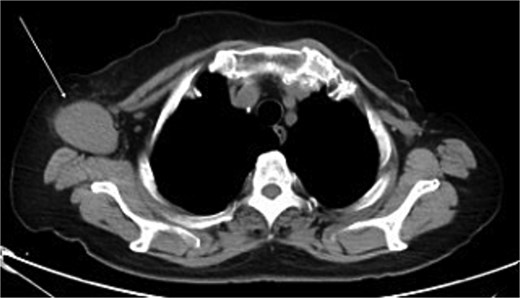

The mammography examination did not reveal any obvious abnormal findings in the right breast (Fig. 1). The breast ultrasound examination also did not reveal any obvious abnormal findings in the breast. The chest computed tomography examination revealed a lymph node that had enlarged to 46 × 34 mm in the right axilla (Fig. 2). There were no enlarged lymph nodes in the mediastinum, hilar region or supraclavicular fossa, and there were no signs of distant metastasis. Magnetic resonance imaging (MRI) of the breast showed no lesions in the right breast, and a lymph node 46 × 34 mm in size was found enlarged in the right axilla (Fig. 3).

Chest computed tomography (CT) findings. A lymph node enlarged to 46 × 34 mm was observed in the right axilla.